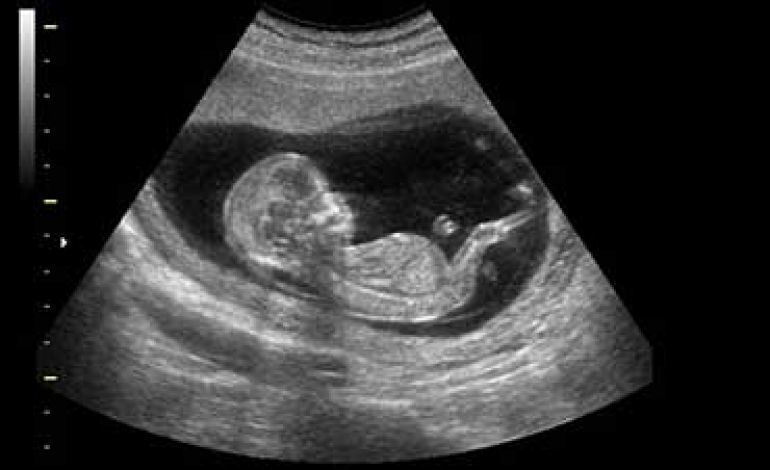

همچنین به طور کلی علم مامایی و زایمان، بارداری و ناباروری، جراحیهای کم تهاجمی، سرطانشناسی زنان از دیگر موضوعات مورد بحث در این کنگره است. چندین کارگاه در زمینه ارتقاء مهارت سونوگرافی و مدیریت خونریزی در سالن زایمان نیز برگزار شده و سمپوزیوم و پنلهای متعددی در راستای رشته تخصصی زنان و زایمان داشتهایم. وی در ادامه درباره انجام سقطهای غیرقانونی هشدار داد و گفت: این مسئله بسیار حائز اهمیت است و این موضوع در کنگره نیز مورد بحث و گفتوگو قرار گرفت.